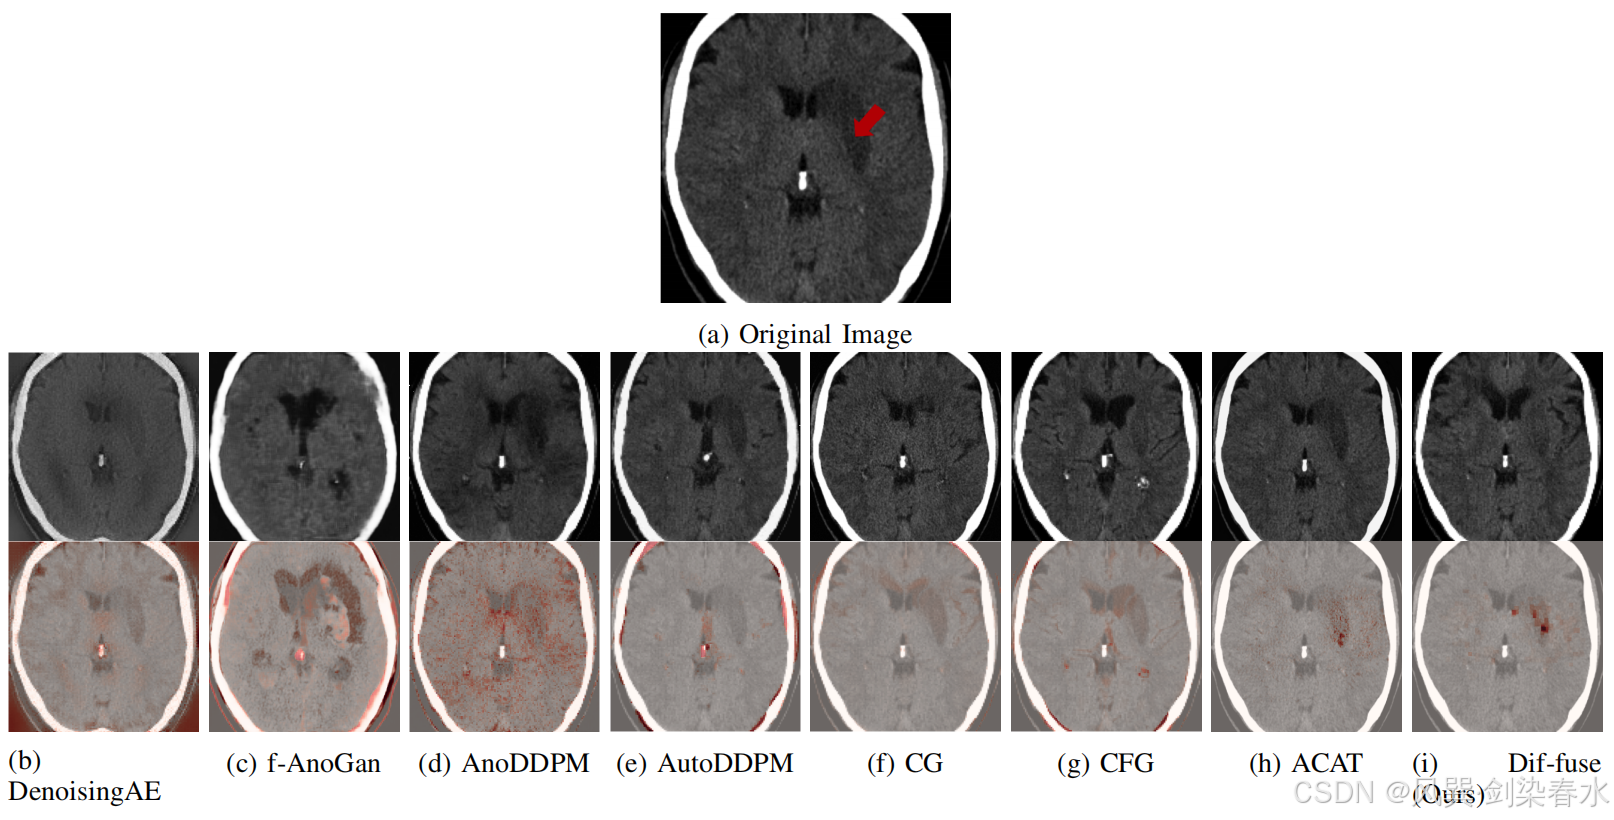

图 2 展示了这一现象,可以看到 ACAT 能够生成一个大致识别出病理区域的显著性图(下面那行)。然而,在反事实示例中,病变仍然可见(上面那行)。相比之下,本文的方法不仅优化了显著性图,还生成了一个病理完全被消除的反事实图像。

Figure 2 | IST-3 的原始图像(a)以及相应的健康反事实图像(第二行)和对应的异常图(底行),这些异常图是通过去噪自编码器(DenoisingAE,b)、f-AnoGAN(c)、AnoDDPM(d)、AutoDDPM(e)、分类器引导(f)、无分类器引导(g)、ACAT(h)和 Dif-fuse(i)获得的:ACAT 生成了一个合理的异常图,但无法完全移除病变。Dif-fuse 在优化 ACAT 获得的异常图的同时,还创建了一个可信的反事实示例。其他方法则引入了伪影和/或对病理区域的识别不够准确;